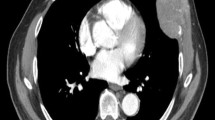

Peritumoral enhancement is defined as the existence of a detectable, arterial-enhancing portion adjacent to, but separate from, the tumor border, as identified on arterial phase images, which later became isointense with the background liver parenchyma in the delayed phase [9]. Further, peritumoral hypointensity on HBP is defined as an irregular, wedge-shaped, or flame-like hypointense area of liver parenchyma located outside of the tumor margin [10]. Their association with MVI has been controversially reported [9, 11,12,13,14,15,16,17]. Hence, we conducted an analysis of the available evidence to reach a more conclusive result considering the relationship between peritumoral imaging features and MVI.

The summary result revealed a significant association between peritumoral enhancement and MVI, with an OR 4.04 [2.23, 7.32], and p < 0.05 (Fig. 2). The inconsistency index I2 was 45.4%, indicating moderate heterogeneity. Meta-regression indicated a possible source of bias in the origin of study (p < 0.05), the imaging test applied (p < 0.05), and the tumor number included (p = 0.02). Subgroup analysis revealed statistically significant results in the group from Korea (OR 7.60 [4.39, 13.17]) and China (OR 2.09 [1.12, 3.92]), and in the solitary (OR 4.32 [1.93, 9.66]) and multiple (OR 3.45 [1.21, 9.78]) tumor groups. When stratified by imaging test, the result of the studies using MRI was statistically significant (OR 4.98 [2.76, 8.99]), but was not significant for those using CT (OR 2.01 [0.62, 6.52]) (Table 2). Sensitivity analysis and Egger’s test showed no small-study effects (p = 0.58). We attempted to apply peritumoral enhancement as the only diagnostic criteria for MVI, which yielded a sensitivity of 0.29 and specificity of 0.90 (Fig. 3). The peritumoral hypointensity on HBP was also significantly associated with MVI, with an OR = 10.62 [5.31, 21.26], and p < 0.05 (Fig. 4). The heterogeneity was low (I2 = 0). A diagnostic analysis revealed similar results with low sensitivity (0.40) and high specificity (0.94) (Fig. 5).

Our meta-analysis indicated significant association between peritumoral imaging features and MVI, but poor diagnostic accuracy. In clinical practice, when MVI is indicated preoperatively, the diagnostic accuracy can be improved with intentional expanded sampling. Adjuvant treatments such as sorafenib [27, 28] or trans-catheter arterial chemoembolization (TACE) [29] can be applied, as these approaches have been reported to improve the survival of HCC patients with MVI. Imaging method has been promising to assess MVI preoperatively, given the discovery of associations between imaging features and proteomics characteristics and gene signatures, and further association with a pathologically diagnosed MVI [30,31,32,33]. Kusano et al. [34] discovered a high level of expression of placental growth factor (PlGF) and vascular endothelial growth factor receptor (VEGFR-1) in adjacent noncancerous tissue associated with MVI. This elevated expression may induce peritumoral pathologic angiogenesis and potentiate vascular invasion [35]. Peritumoral enhancement may represent compensatory arterial hyperperfusion, after changes in hemodynamic perfusion with obstruction of the peritumoral microvessels by tumor thrombi [36]. Peritumoral hypointensity on HBP reflects decreased peritumoral uptake of the contrast agent on MRI. Nishie [37] suggested that this finding may be caused by Kupffer cells and hepatocyte injury in tumorous AP shunts in which the associated portal branches are obstructed.